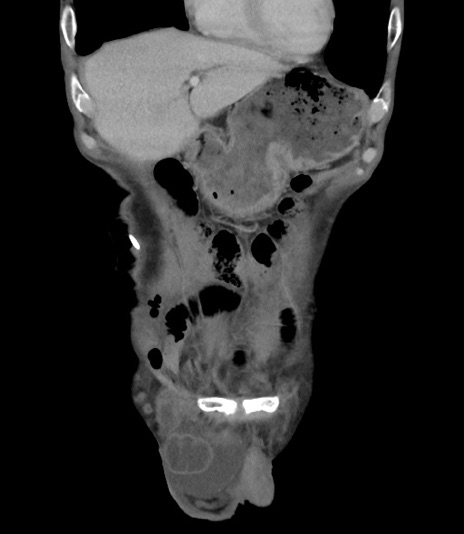

症例3(冠状断像)

【症例】 70歳代男性

【主訴】右鼠径部腫瘤、疼痛

【現病歴】本日朝より上記主訴あり、受診。

【既往歴】膀胱癌にて膀胱全摘、両側尿管皮膚瘻

【データ】WBC 5600、CRP 0.56